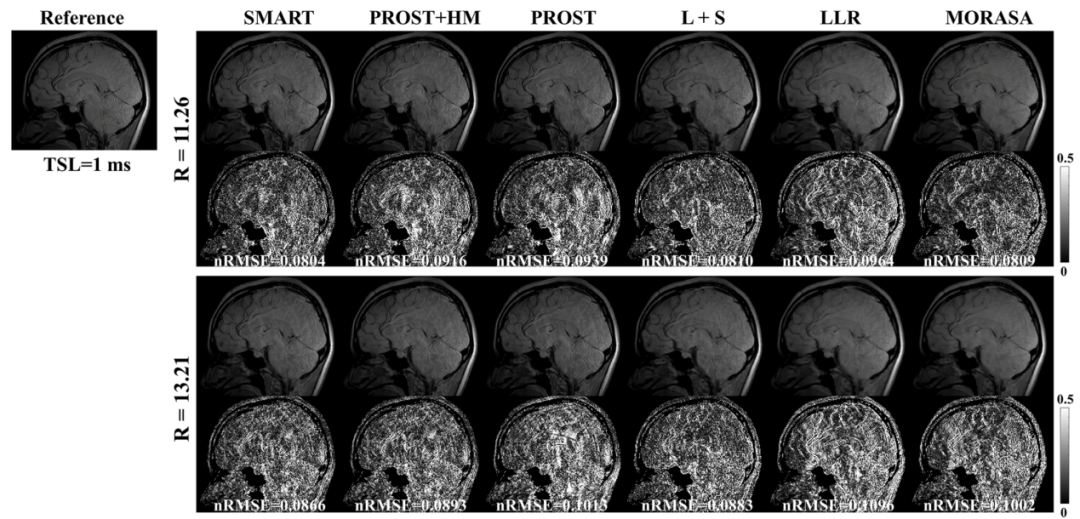

此外,磁共振驰豫值是其重要的物理参数,可以表征组织的一些生理信息,团队基于该物理弛豫先验和图像的结构相似性,提出了基于低秩张量的快速磁共振T1ρ驰豫定量方法(SMART),将扫描时间由全采样数据所需的49.9分钟缩短至3.8分钟,且在高达13.2倍加速倍数下仍能取得与全采样数据相当的图像,且重建误差小于现在主流的重建方法(图3)。相关研究工作发表在医学成像领域著名期刊IEEE Transactions on Medical Imaging

图3.不同加速倍数下(R=11.26, 13.21)所提的SMART方法与其他主流方法的重建结果对比。